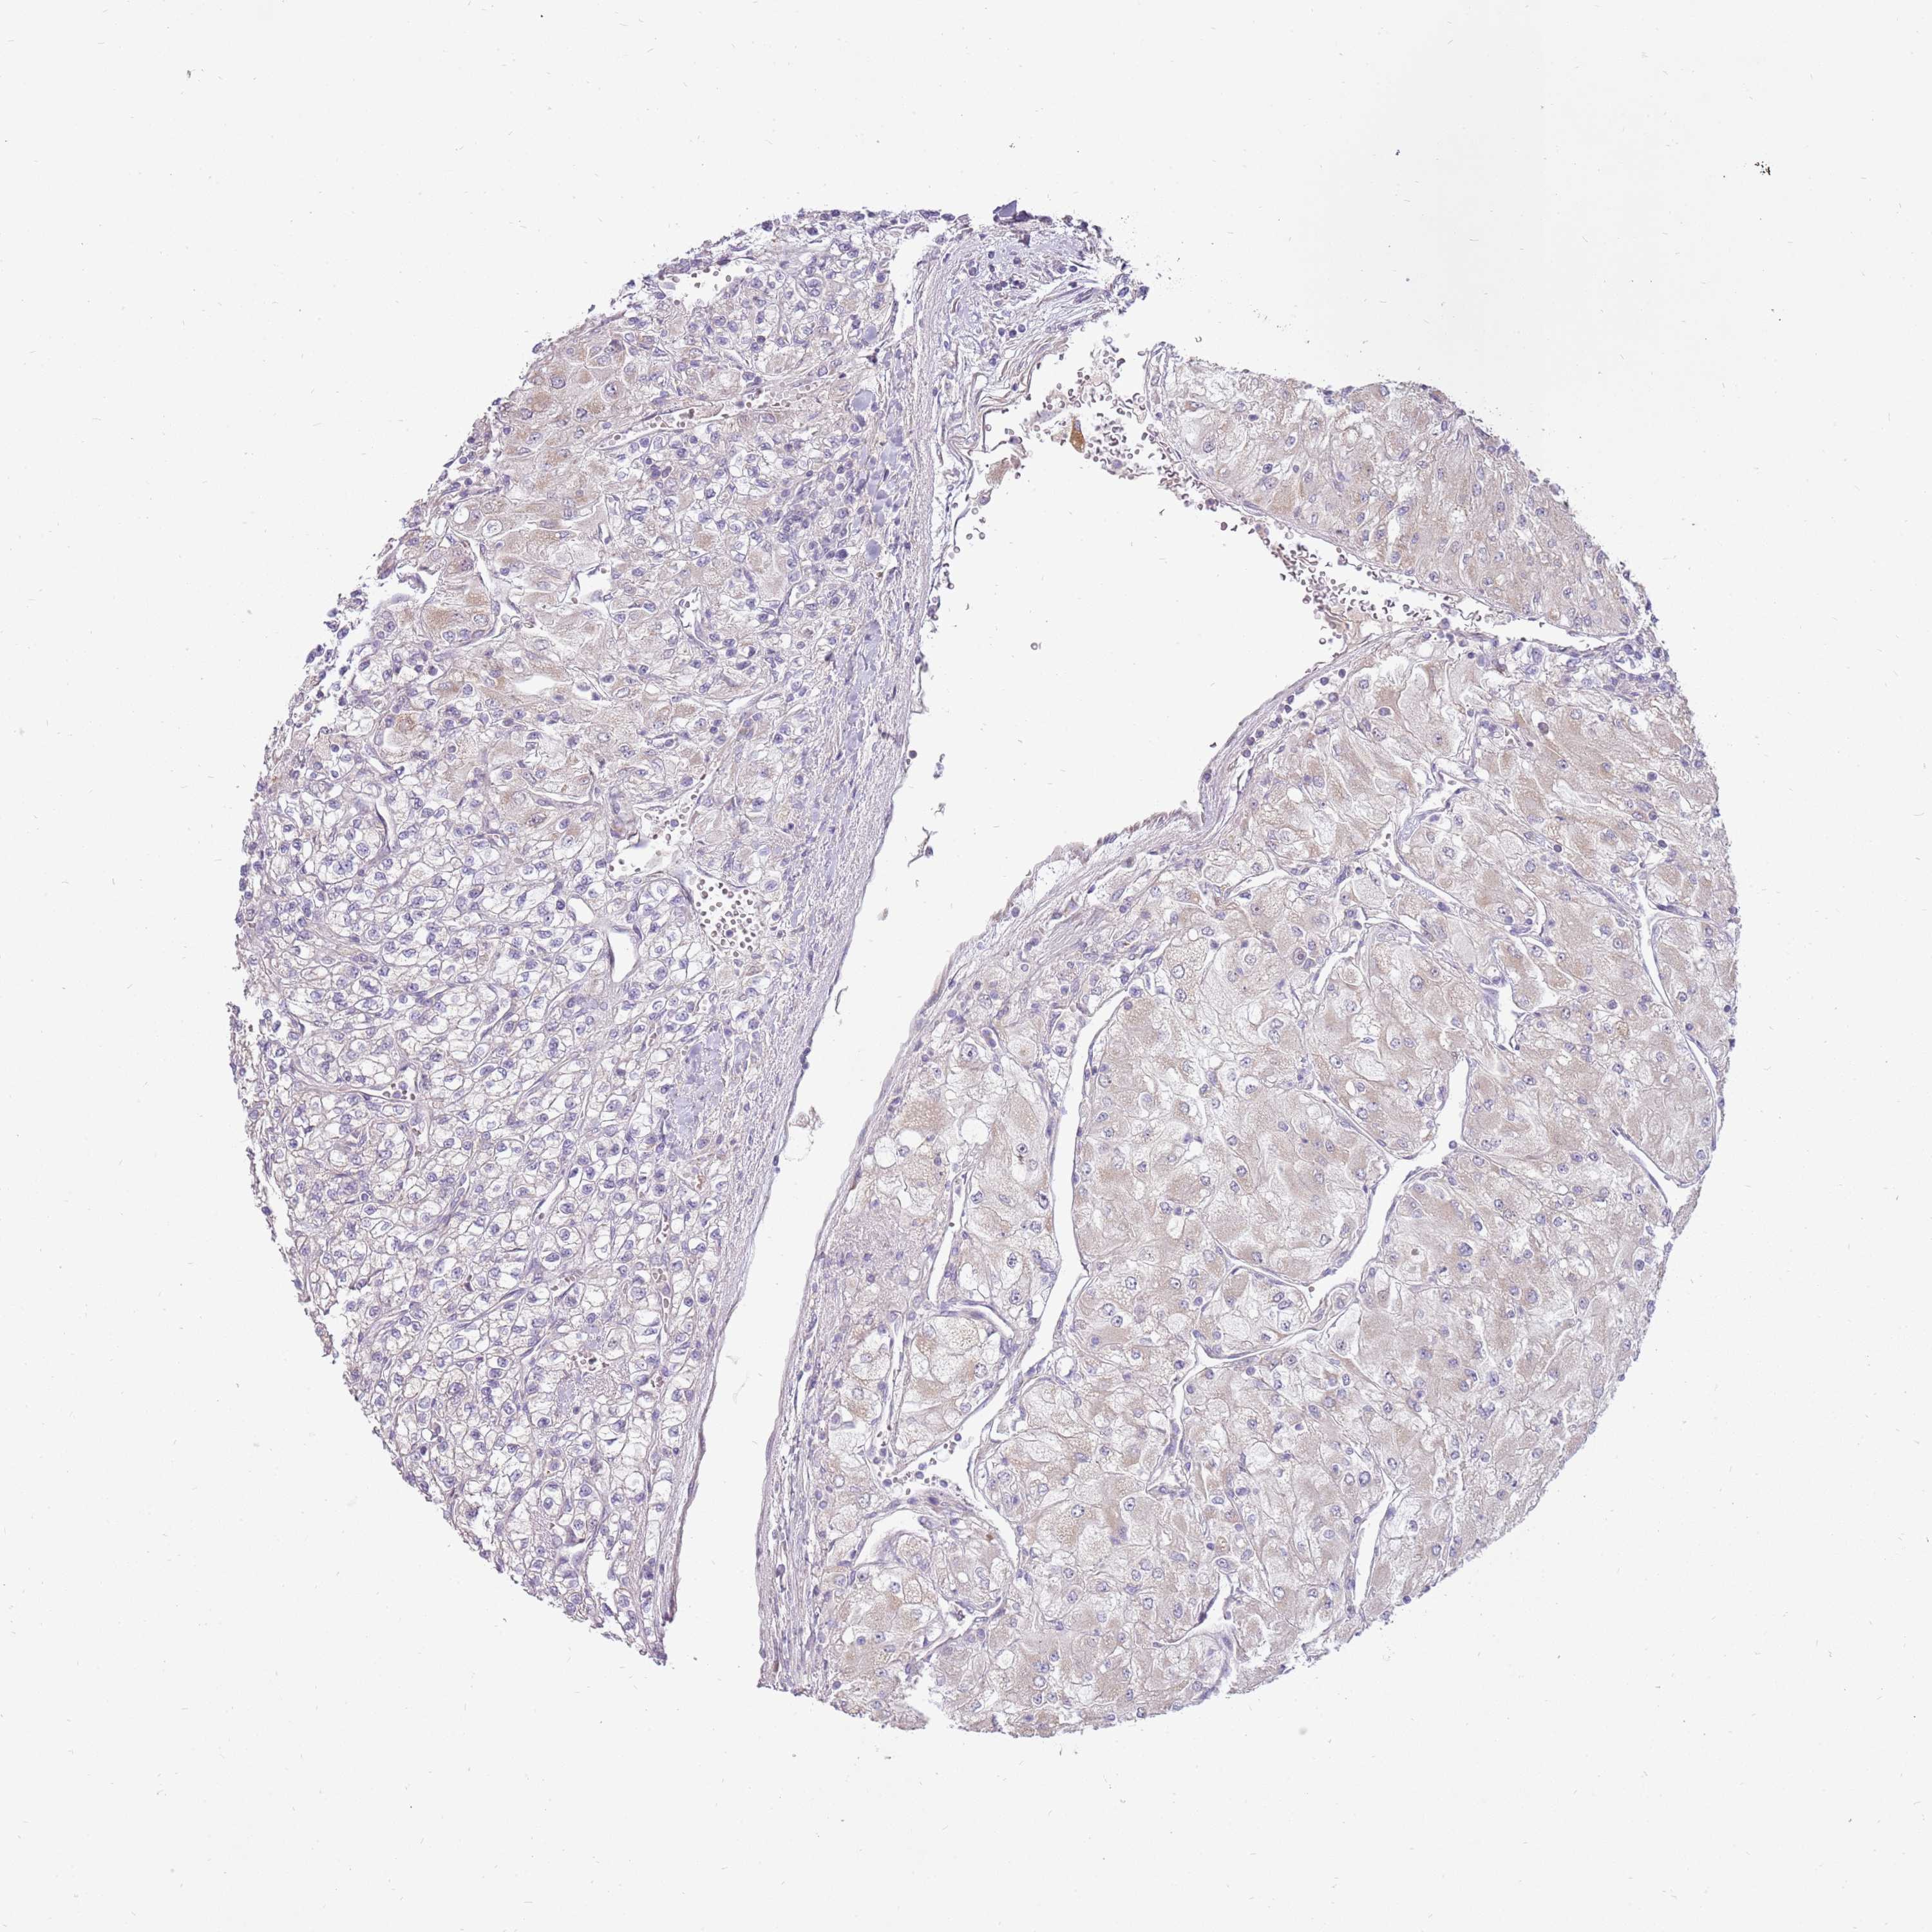

KIDNEY RENAL CLEAR CELL CARCINOMA (TCGA) - Interactive survival scatter ploti

The Survival Scatter plot shows the clinical status (i.e. dead or alive) for all individuals in the patient cohort, based on the same data that underlies the corresponding Kaplan-Meier plots. Patients that are alive at last time for follow-up are shown in blue and patients who have died during the study are shown in red.

The x-axis shows the expression levels (FPKM) of the investigated gene in the tumor tissue at the time of diagnosis. The y-axis shows the follow-up time after diagnosis (years). Both axes are complimented with kernel density curves demonstrating the data density over the axes. The top density plot shows the expression levels (FPKM) distribution among dead (red) and alive patients (blue). The right density plot shows the data density of the survived years of dead patients with high and low expression levels respectively, stratified using the cutoff indicated by the vertical dashed line through the Survival Scatter plot. This cutoff is automatically defined based on the FPKM cutoff that minimizes the p-score. The cutoff can be changed by dragging the vertical line or by entering a cutoff value in the square labeled "Current cut-off".

Under the Survival Scatter plot the p-score landscape (black curve; left axis) is shown together with dead median separation (red curve; right axis). Dead median separation is the difference in median mRNA expression between patients who have died with high and low expression, respectively. It is calculated as follows: median FPKM expression of dead patients with high expression - median FPKM expression of dead patients with low expression. This is intended to aid the user in visually exploring custom cutoffs and the associated p-scores and dead median separation.

Individual patient data is displayed and can be filtered by clicking on one or more of the category buttons on the top of the page. Categories describing expression level and patient information include: high, low, alive, dead, female, male and tumor stages. The scale of the x-axis can be toggled between linear and log-scale by clicking on the "x log" button. Mouse-over function shows TCGA ID, patient information and mRNA expression (FPKM) for each patient.

& Survival analysisi

Kaplan-Meier plots summarize results from analysis of correlation between mRNA expression level and patient survival. Patients were divided based on level of expression into one of the two groups "low" (under cut off) or "high" (over cut off). X-axis shows time for survival (years) and y-axis shows the probability of survival, where 1.0 corresponds to 100 percent.

LRFN3 is not prognostic in Kidney Renal Clear Cell Carcinoma (TCGA)

Best expression cut offi

Based on the FPKM value of each gene, patients were classified into two groups and association between prognosis (survival) and gene expression (FPKM) was examined. The best expression cut-off refers the FPKM value that yields maximal difference with regard to survival between the two groups at the lowest log-rank P-value. Best expression cut-off was selected based on survival analysis .

When clicking on this number, the vertical dashed line indicating cut-off, the interactive survival plot, and the Kaplan-Meier curve will be adjusted to show results based on the best expression cut-off.

: 1.92

P scorei

Log-rank P value for Kaplan-Meier plot showing results from analysis of correlation between mRNA expression level and patient survival.

N/A

TCGA RNA samplesi

RNA-seq data is reported as average FPKM (number Fragments Per Kilobase of exon per Million reads), generated by the The Cancer Genome Atlas (TCGA) .

Normal distribution across the dataset is visualized with box plots, shown as median and 25th and 75th percentiles. Points are displayed as outliers if they are above or below 1.5 times the interquartile range. FPKM values of the individual samples are presented next to the box plot.

Average pTPM 2.9

Number of samples 521